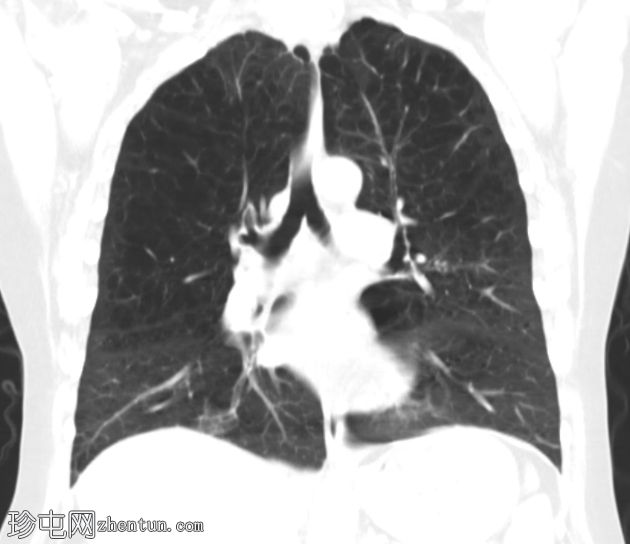

双侧肺(尤其是上叶)广泛融合性小叶中心型肺气肿。

左上叶肺瘢痕形成,可能是先前感染的后遗症。

双侧乳房植入。

早期小叶中心性肺气肿通常表现为小(<1 mm 至 3 cm)、圆形、均匀分布、边界不清的透亮区,可能出现在小叶中心动脉周围的次级肺小叶中央部分,而在严重的情况下,低衰减区会融合且不可分离,并且失去小叶中心分布。